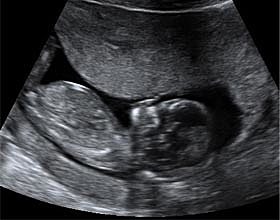

El embrión mide entre 2 y 3 centímetros en la semana 9 de embarazo y su forma ya es mucho más parecida a un ser humano: Aparecen las manos con los dedos y las muñecas, Las piernas se alargan aparecen los pies con sus dedos correspondientes. La cabeza sigue siendo la parte más grande en proporción con el resto del cuerpo los párpados cubren parcialmente los ojos. Los pabellones auriculares están bien formados. La boca se aprecia e incluso se abre.